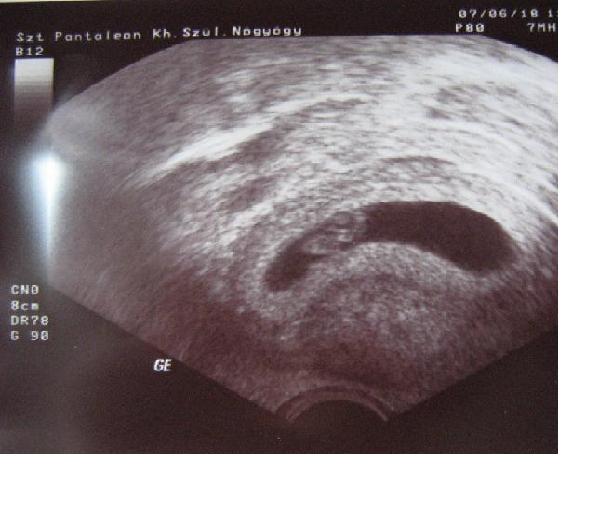

Voltam ma UH-on. :D Minden rendben van! :D Már lehetet látni és hallani a szívdobogását! :D Annyira hihetetlen! Kaptam képet is. A mai nap folyamán még megpróbálom felvarázsolni ide.

Vonalzót is kreálok majd egy újat. UH alapján 7 hetes.